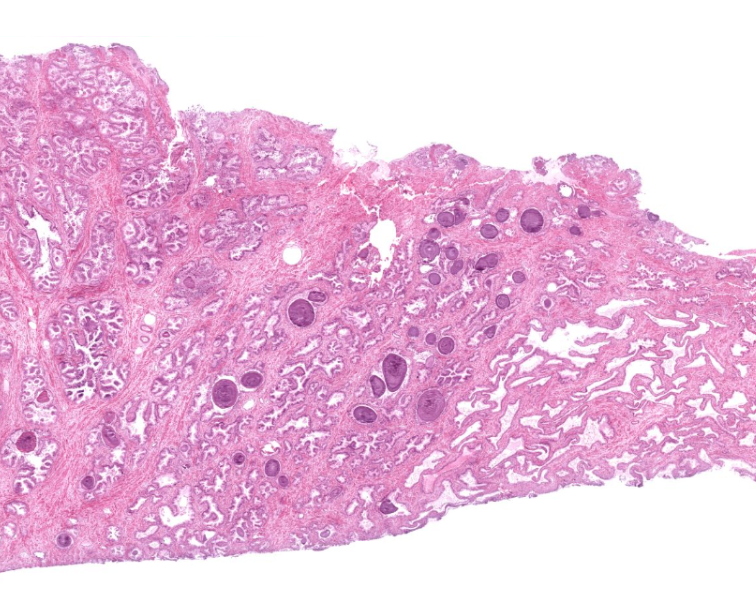

prostate gland

secretes prostatic fluid???

identifiable by the dark purple structures